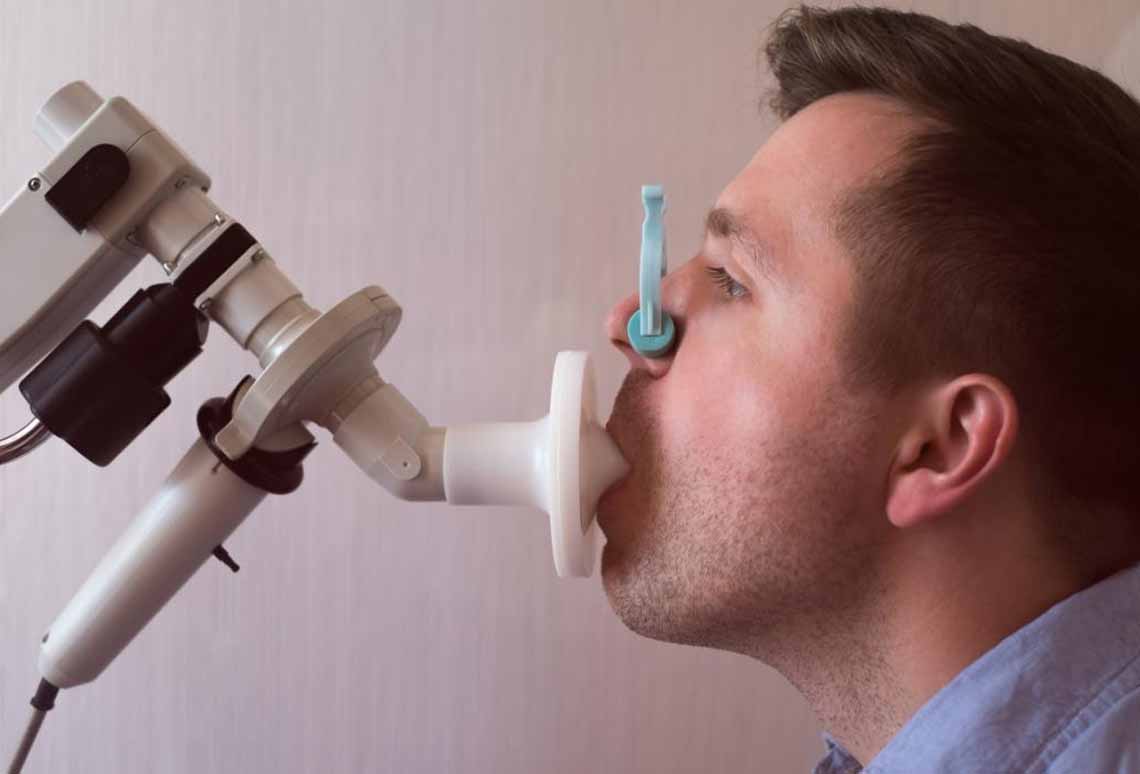

» Specialist in : Respiratory & Sleep Disorders

Asthma / Bronchitis

COPD

Chronic obstructive pulmonary disease, or COPD, is a group of progressive lung diseases. The most common are emphysema and chronic bronchitis.